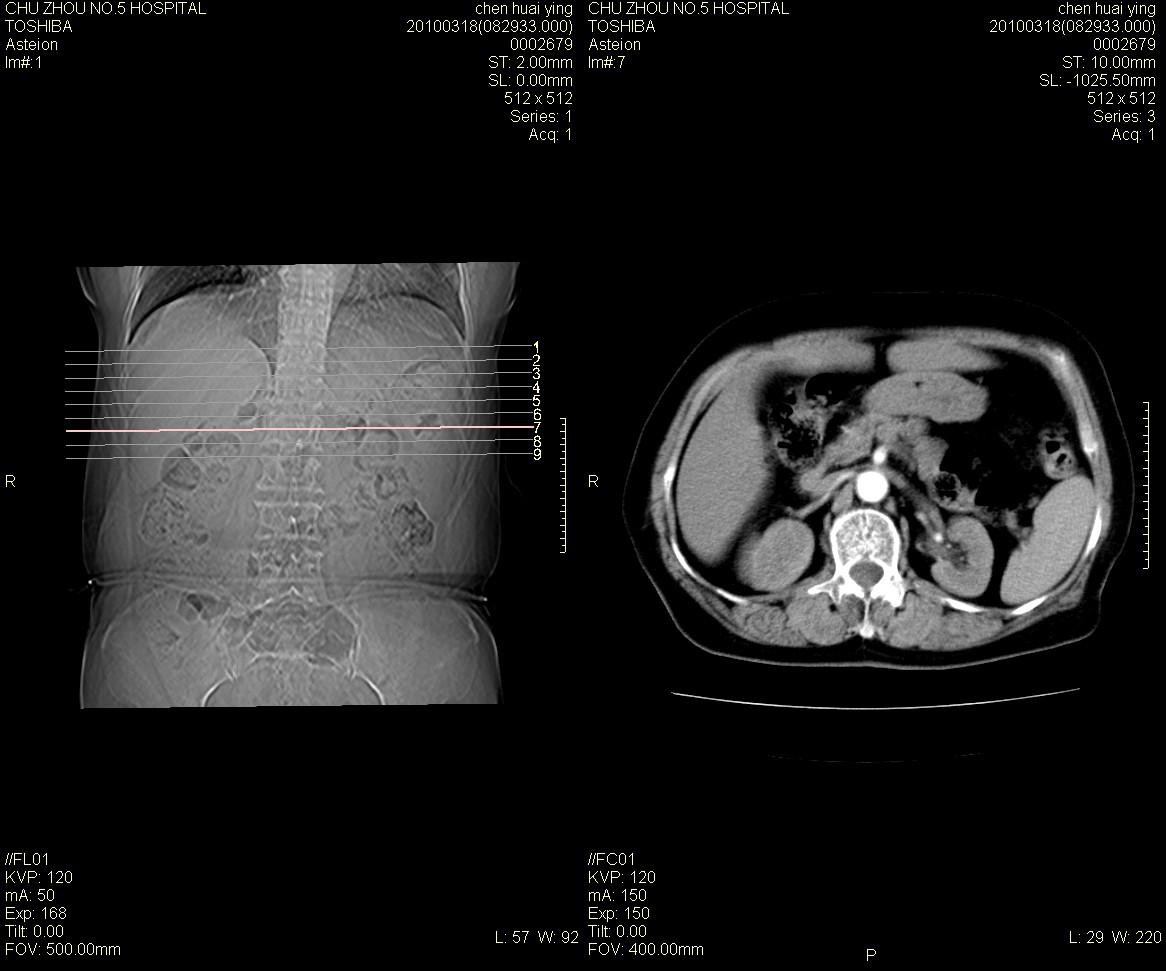

标题: CT25148 肾上腺增强

ct25148增强图片

动脉期太早了,扫的有点低。考虑良性占位右侧肾上腺嗜铬细胞瘤并坏死囊变可能性大,神经鞘瘤不排除。

右侧肾上腺占位性病变,病人是否有高血压?嗜铬细胞瘤?

右侧肾上腺嗜铬细胞瘤并坏死囊变可能性大